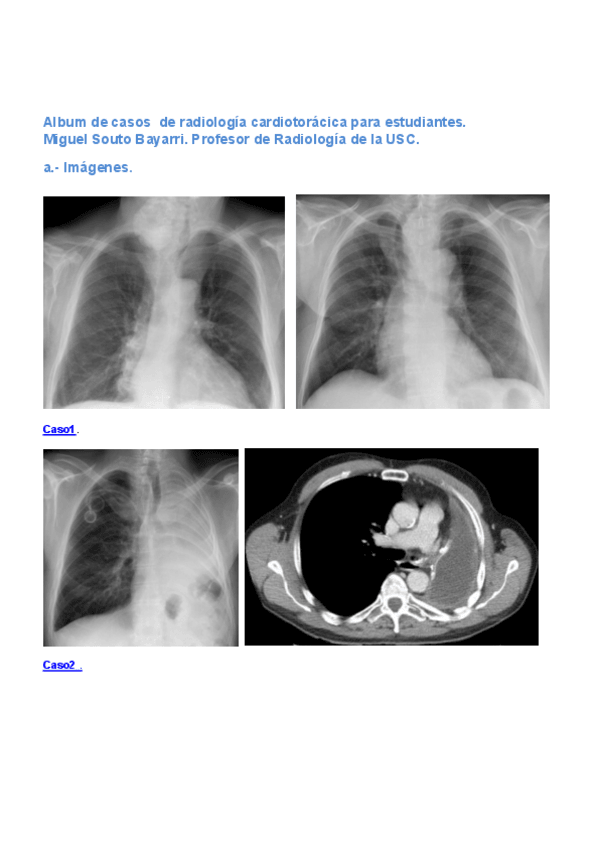

Exámenes - Album-de-casos-de-radiologia-cardiotoracica-para-estudiantes.-Miguel-Souto-Bayarri.-Profesor-de-Radiologia-de-la-USC..pdf